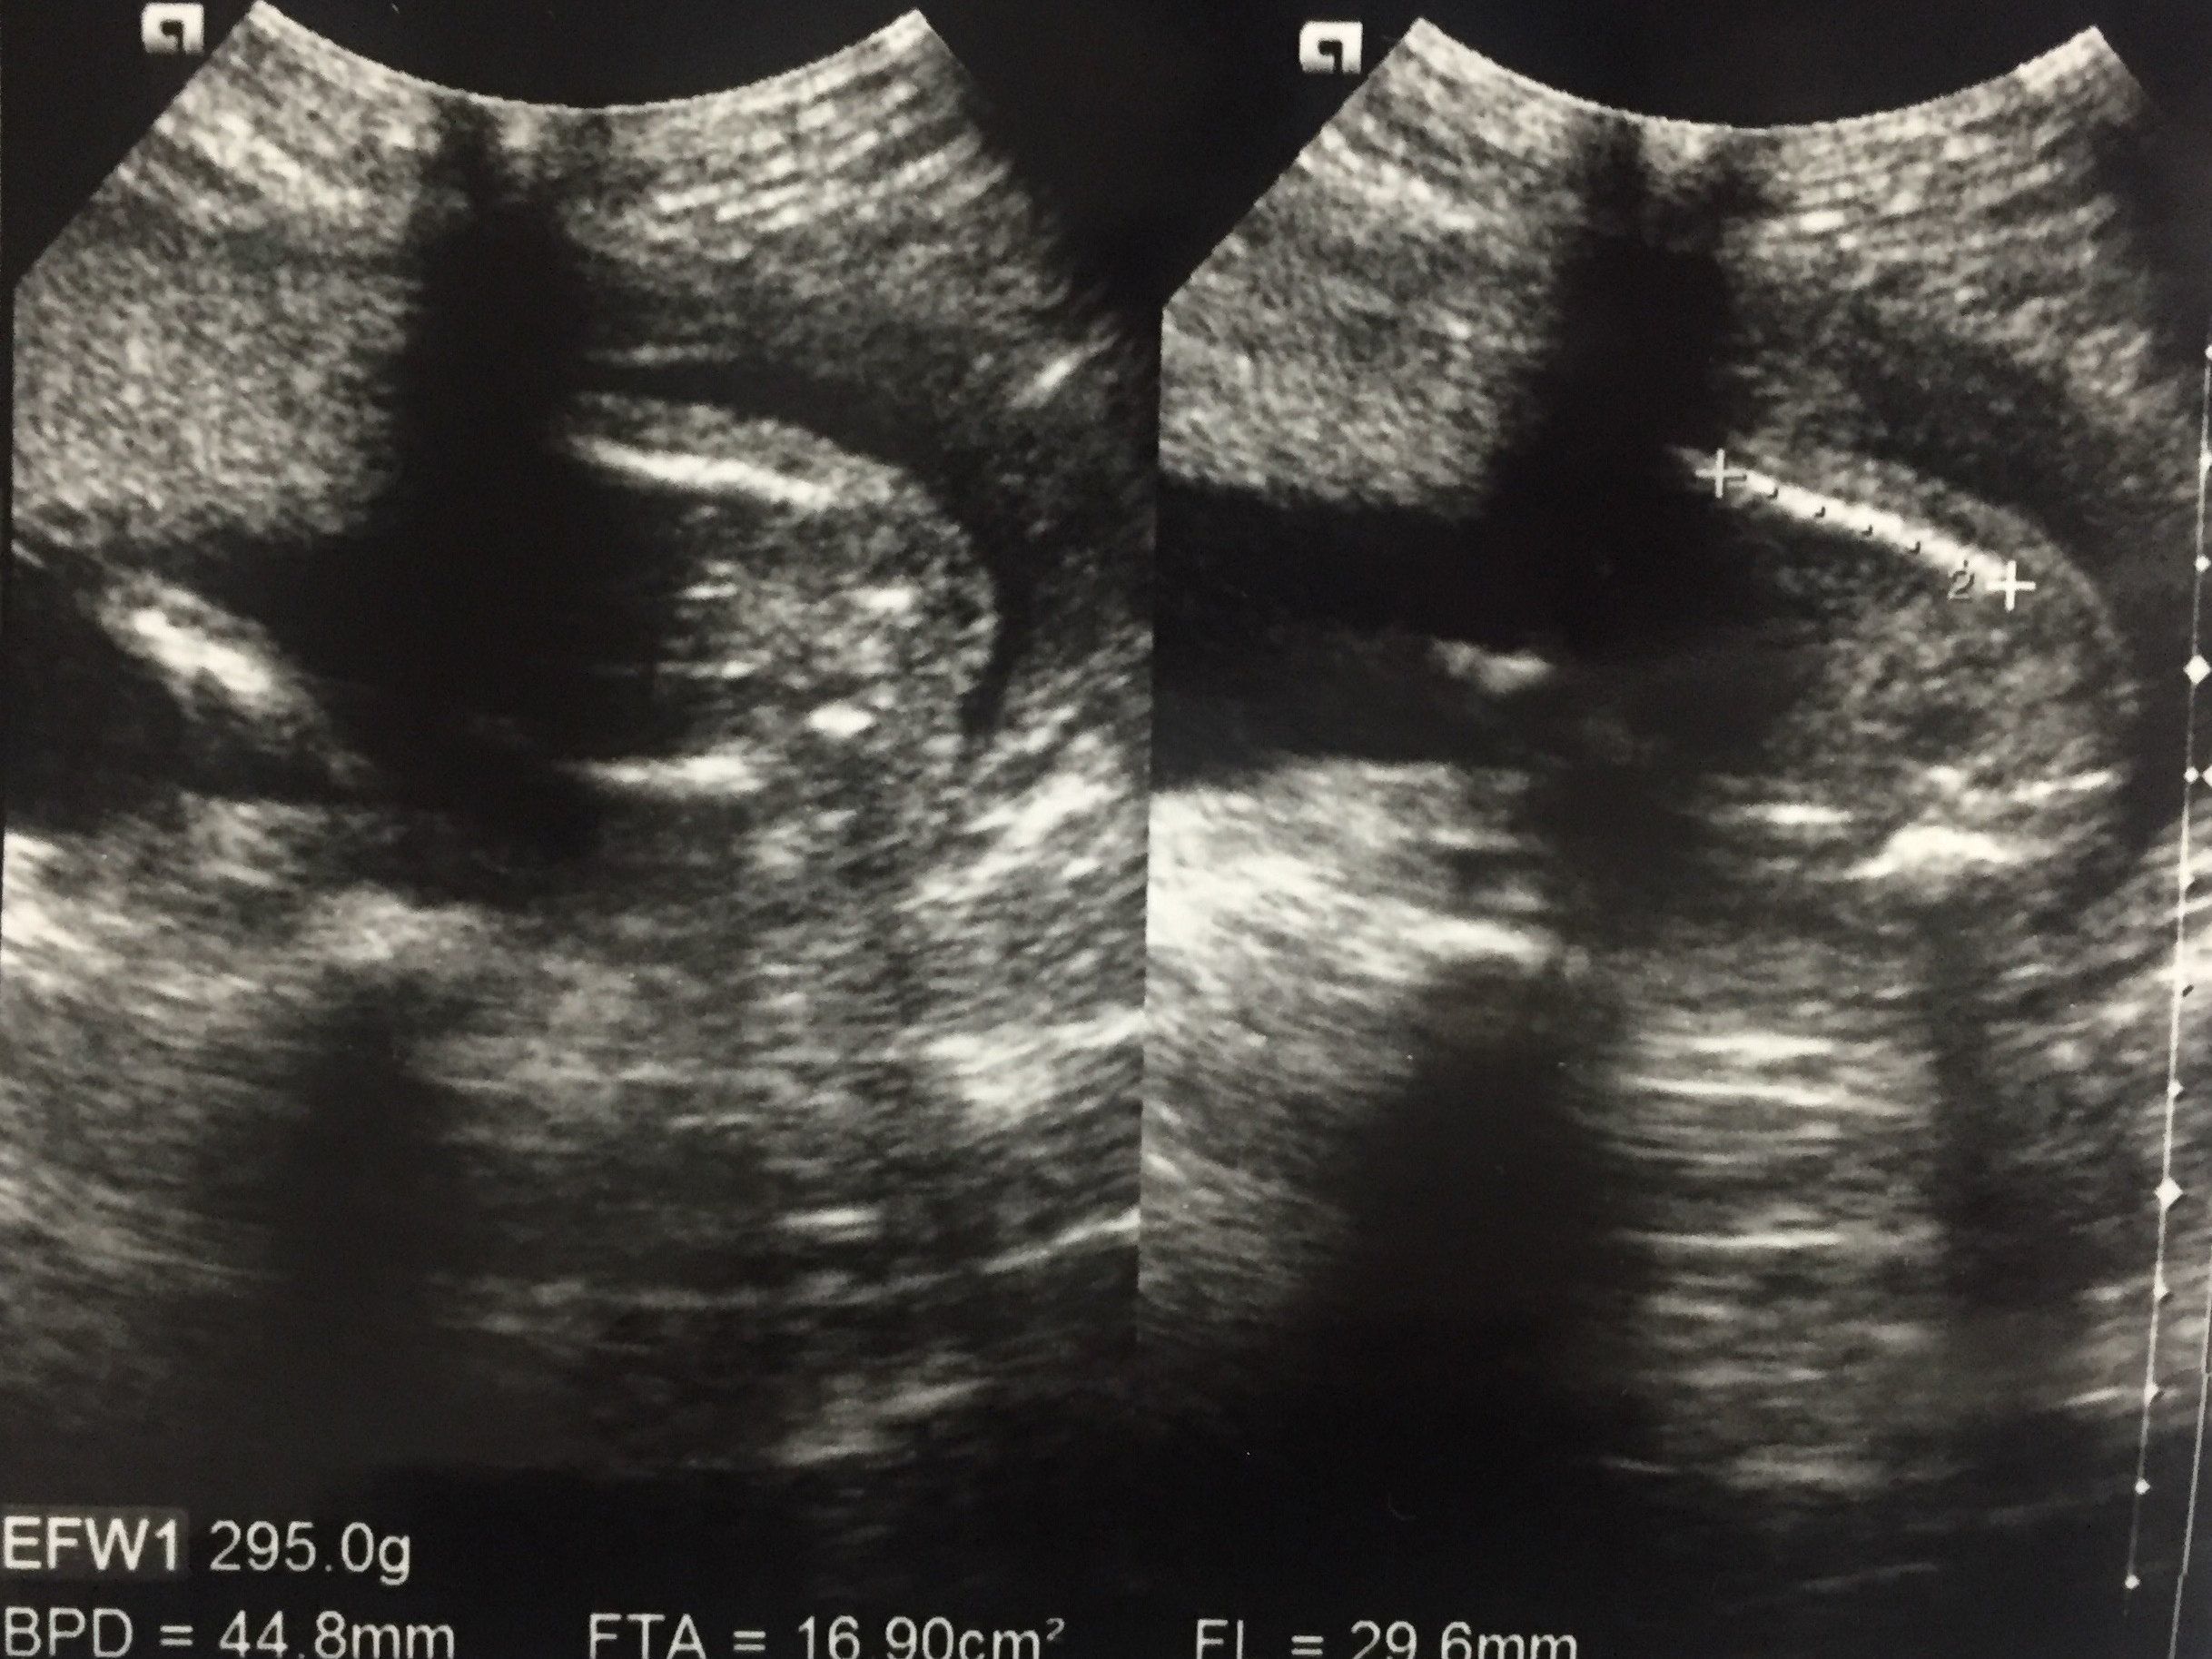

妊娠22週目 胎動が感じられるようになり、安心で幸せ

この写真も赤ちゃんをお尻側から撮影したもので、右の方に足が2本伸びています。足と足の間を見ると、男の子だろうということがわかります。

毎日胎動を感じるたびに「赤ちゃんが元気でいてくれている」と自分で確認ができ、安心で幸せな気持ちでした。

性別もわかり、どんな名前にしようかと夫と相談を始めました。買うべき赤ちゃん用品をリサーチするのも楽しかったです。